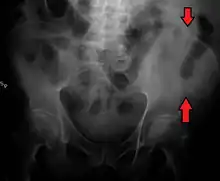

A fracture of the left iliac wing

The iliac crest has a large amount of red bone marrow, and thus it is the site of bone marrow harvests (from both sides) to collect the stem cells used in bone marrow transplantation. The iliac crest is also considered the best donor site for bone grafting when a large quantity of bone is needed. For example, oral and maxillofacial surgeons will often use iliac crest bone to fill in large osseous defects of the oral cavity caused by severe periodontal disease, excess bone resorption following tooth loss, trauma, or congenital defects including alveolar clefts.[4]

The top of the iliac crests also marks the level of the fourth lumbar vertebral body (L4), above or below which lumbar puncture may be performed. Furthermore, said level is often referred to as the "intercristal line".